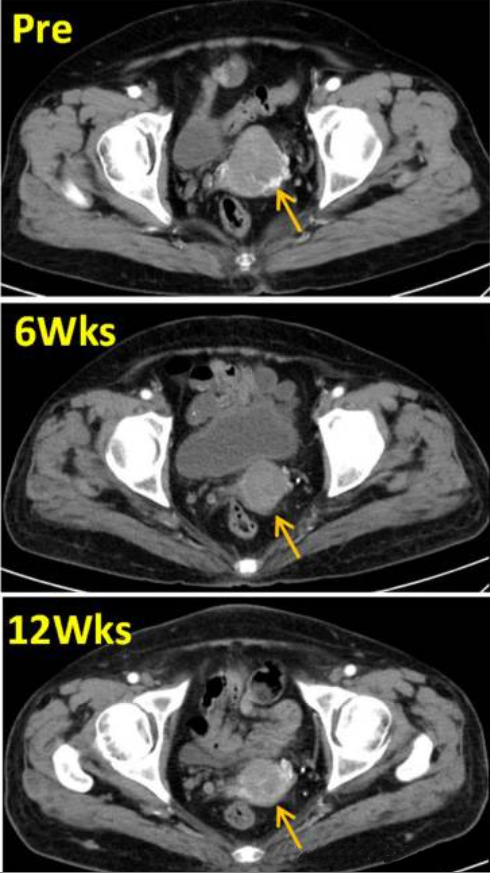

宫颈癌是女性常见的恶性肿瘤之一,传统的放疗和化疗虽然在一定程度上能够控制病情,但长期效果并不理想,TIL疗法在这一领域的应用也展现出了良好的前景。2024年初,《International Journalof Women's Health》在线发布了一项TIL细胞治疗宫颈癌的病例报告,一名IV期宫颈癌患者在TIL细胞治疗6周后,肿瘤缩小至3.3厘米,12周后肿瘤缩小了33%,这一案例表明,TIL疗法在宫颈癌治疗中具有一定的疗效,值得进一步研究和推广。

图片来源:参考资料4